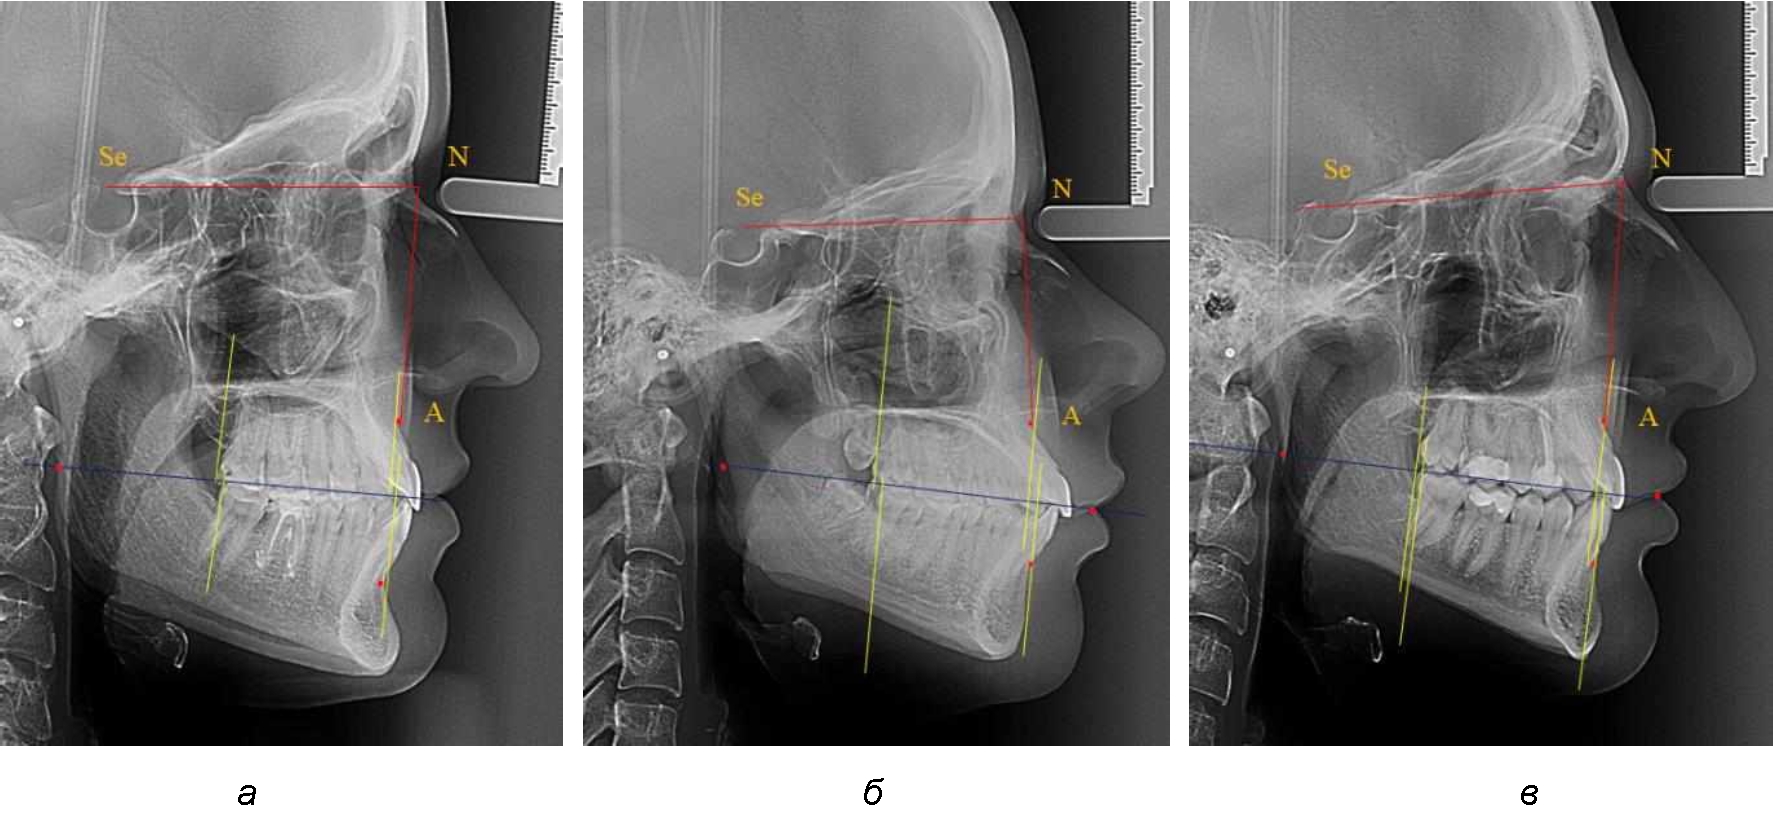

На рентенограммах с признаками дистальной окклюзии Wits-число имело положительные значения. Дистальная точка нижнего моляра была расположена позади верхней дистальной точки окклюзии второго моляра. Относительно равными, так же как и при анализе снимков с мезиальной окклюзией, считались показатели альвеолярно-дентальных размеров, при которых разница не превышала 1,5 мм. Тем не менее расстояние «rmРOcP-A(SS)» превышало расстояние «rmРOcP-B(SM)» в среднем по группе на (5,29 ± 1,47) мм (рис. 4).

Рис. 4. Положение апикальных точек и челюстей при дистальной окклюзии с равными (а) и разными (б) альвеолярно-дентальными размерами зубочелюстных дуг

В тех случаях, когда при дистальной окклюзии альвеолярно-дентальные размеры были различными, размер нижней челюсти превышал аналогичный параметр верхней челюсти, в среднем на (3,62 ± 1,12) мм.